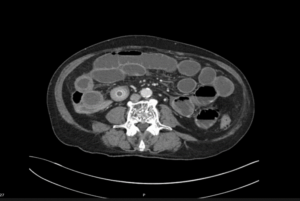

A 92-year-old man presented to emergency with abdominal pain, vomiting and fever. He had been experiencing 24 hours of abdominal pain which had become significantly worse in the last 3 hours. He has generalized abdominal tenderness and distention. Lactate is 2.5 and he has a mild AKI.

EXPLANATION -There are multiple dilated loops of small bowel secondary to small bowel obstruction. There is mild mural thickening in the right lower quadrant, suggestive of early ischemia. An abrupt transition is seen in the terminal ileum due to a 30 mm gallstone – a gallstone ileus.

Pneumobilia is present, this is secondary to a cholecystoduodenal fistula.

Gallstone ileus is an uncommon but potentially serious cause of small bowel obstruction.

- It occurs when a gallstone enters the small bowel via a biliary-enteric fistula, causing a mechanical bowel obstruction.

- The site of obstruction is the terminal ileum in 50-70% cases (as in this case), 90% of stones over 2cm in diameter cause obstruction. There may be colicky, often periumbilical, abdominal pain, distension, constipation, nausea and vomiting.

- Current surgical options are simple enterolithotomy (as in this case); enterolithotomy, cholecystectomy and fistula closure (one-stage procedure) or enterolithotomy with cholecystectomy performed later as a two-stage procedure.

- This patient went for urgent laparotomy. A 3cm gallstone was found in the distal ileum. The gallstone was able to be moved proximally, and an enterotomy was performed for removal of the gallstone via the ileum.